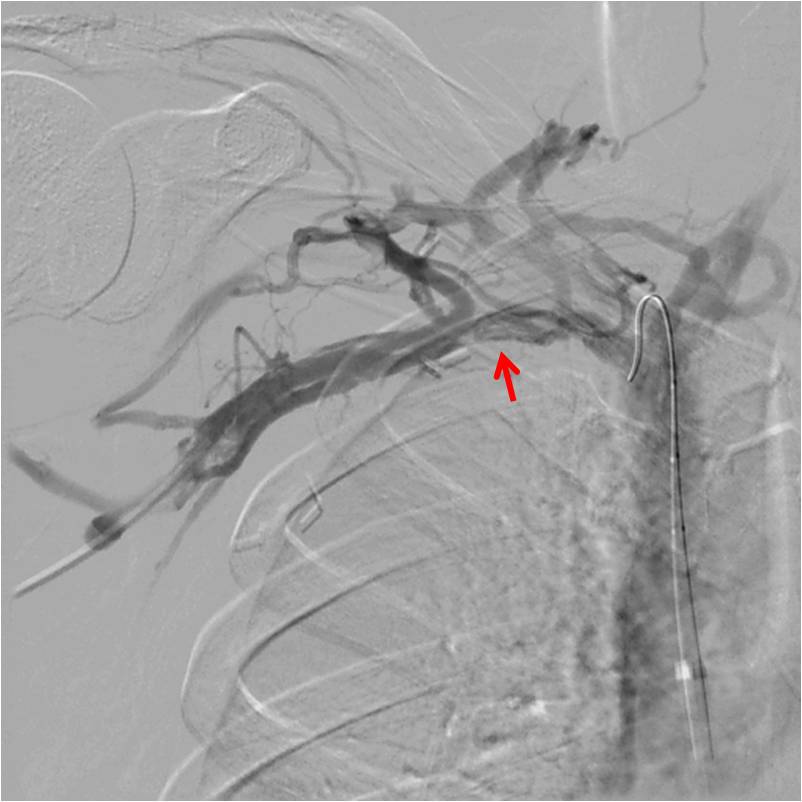

Venography is recommended in two instances. First, if the diagnosis is suspected, but proof was not obtained otherwise. For instance, when the duplex is inconclusive. The second use for venography, of course, is during a procedure. Venography often reveals venous collaterals, suggesting chronic sub-total compressions have been present. Furthermore, venography can be performed when the hand is in the neutral position or abducted. If extrinsic compression is visible, that suggests Paget Schroetter. Surprisingly CT and MR are not well suited imaging modalities for diagnosing Paget Schroetter, despite their obvious capabilities in diagnosing clot per se.